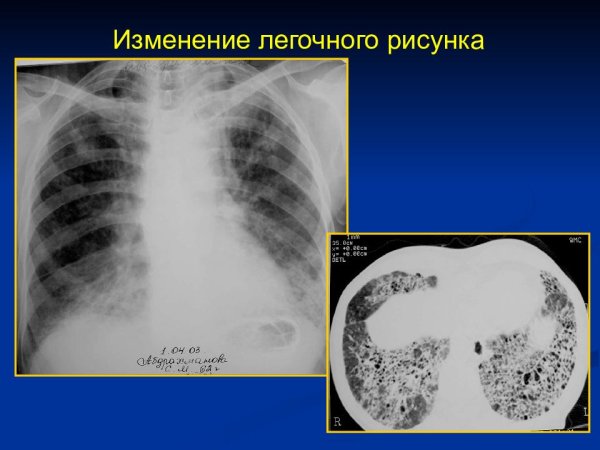

Изменение легочного рисунка

Патология легочного рисунка - это состояние, при котором обнаруживается изменение образца распределения сосудистых и бронхиальных структур в легких. Это может быть вызвано различными причинами, такими как хронические заболевания легких, врожденные аномалии или инфекционные процессы. При патологии легочного рисунка могут наблюдаться различные изменения на рентгенограммах, такие как утолщение сосудов, усиление бронхиального образца или появление тени. Диагностика и лечение этого состояния требуют комплексного подхода, основанного на клинических данных и дополнительных исследованиях. Целью такого лечения является устранение основной причины патологии легочного рисунка и восстановление нормальной структуры и функции легких.